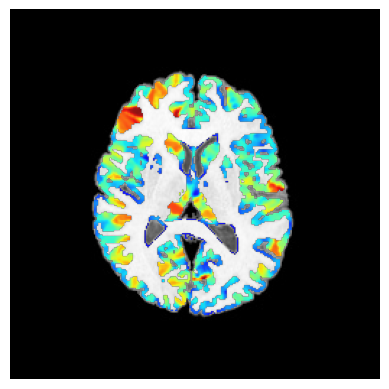

stderr 2025-11-10T00:50:59.619948:*+ WARNING: If you are performing spatial transformations on an oblique dset,

251110-00:50:59,620 nipype.interface INFO:

stderr 2025-11-10T00:50:59.619948: such as ds001226/sub-CON02/ses-preop/anat/sub-CON02_ses-preop_T1w.nii.gz,

251110-00:50:59,621 nipype.interface INFO: